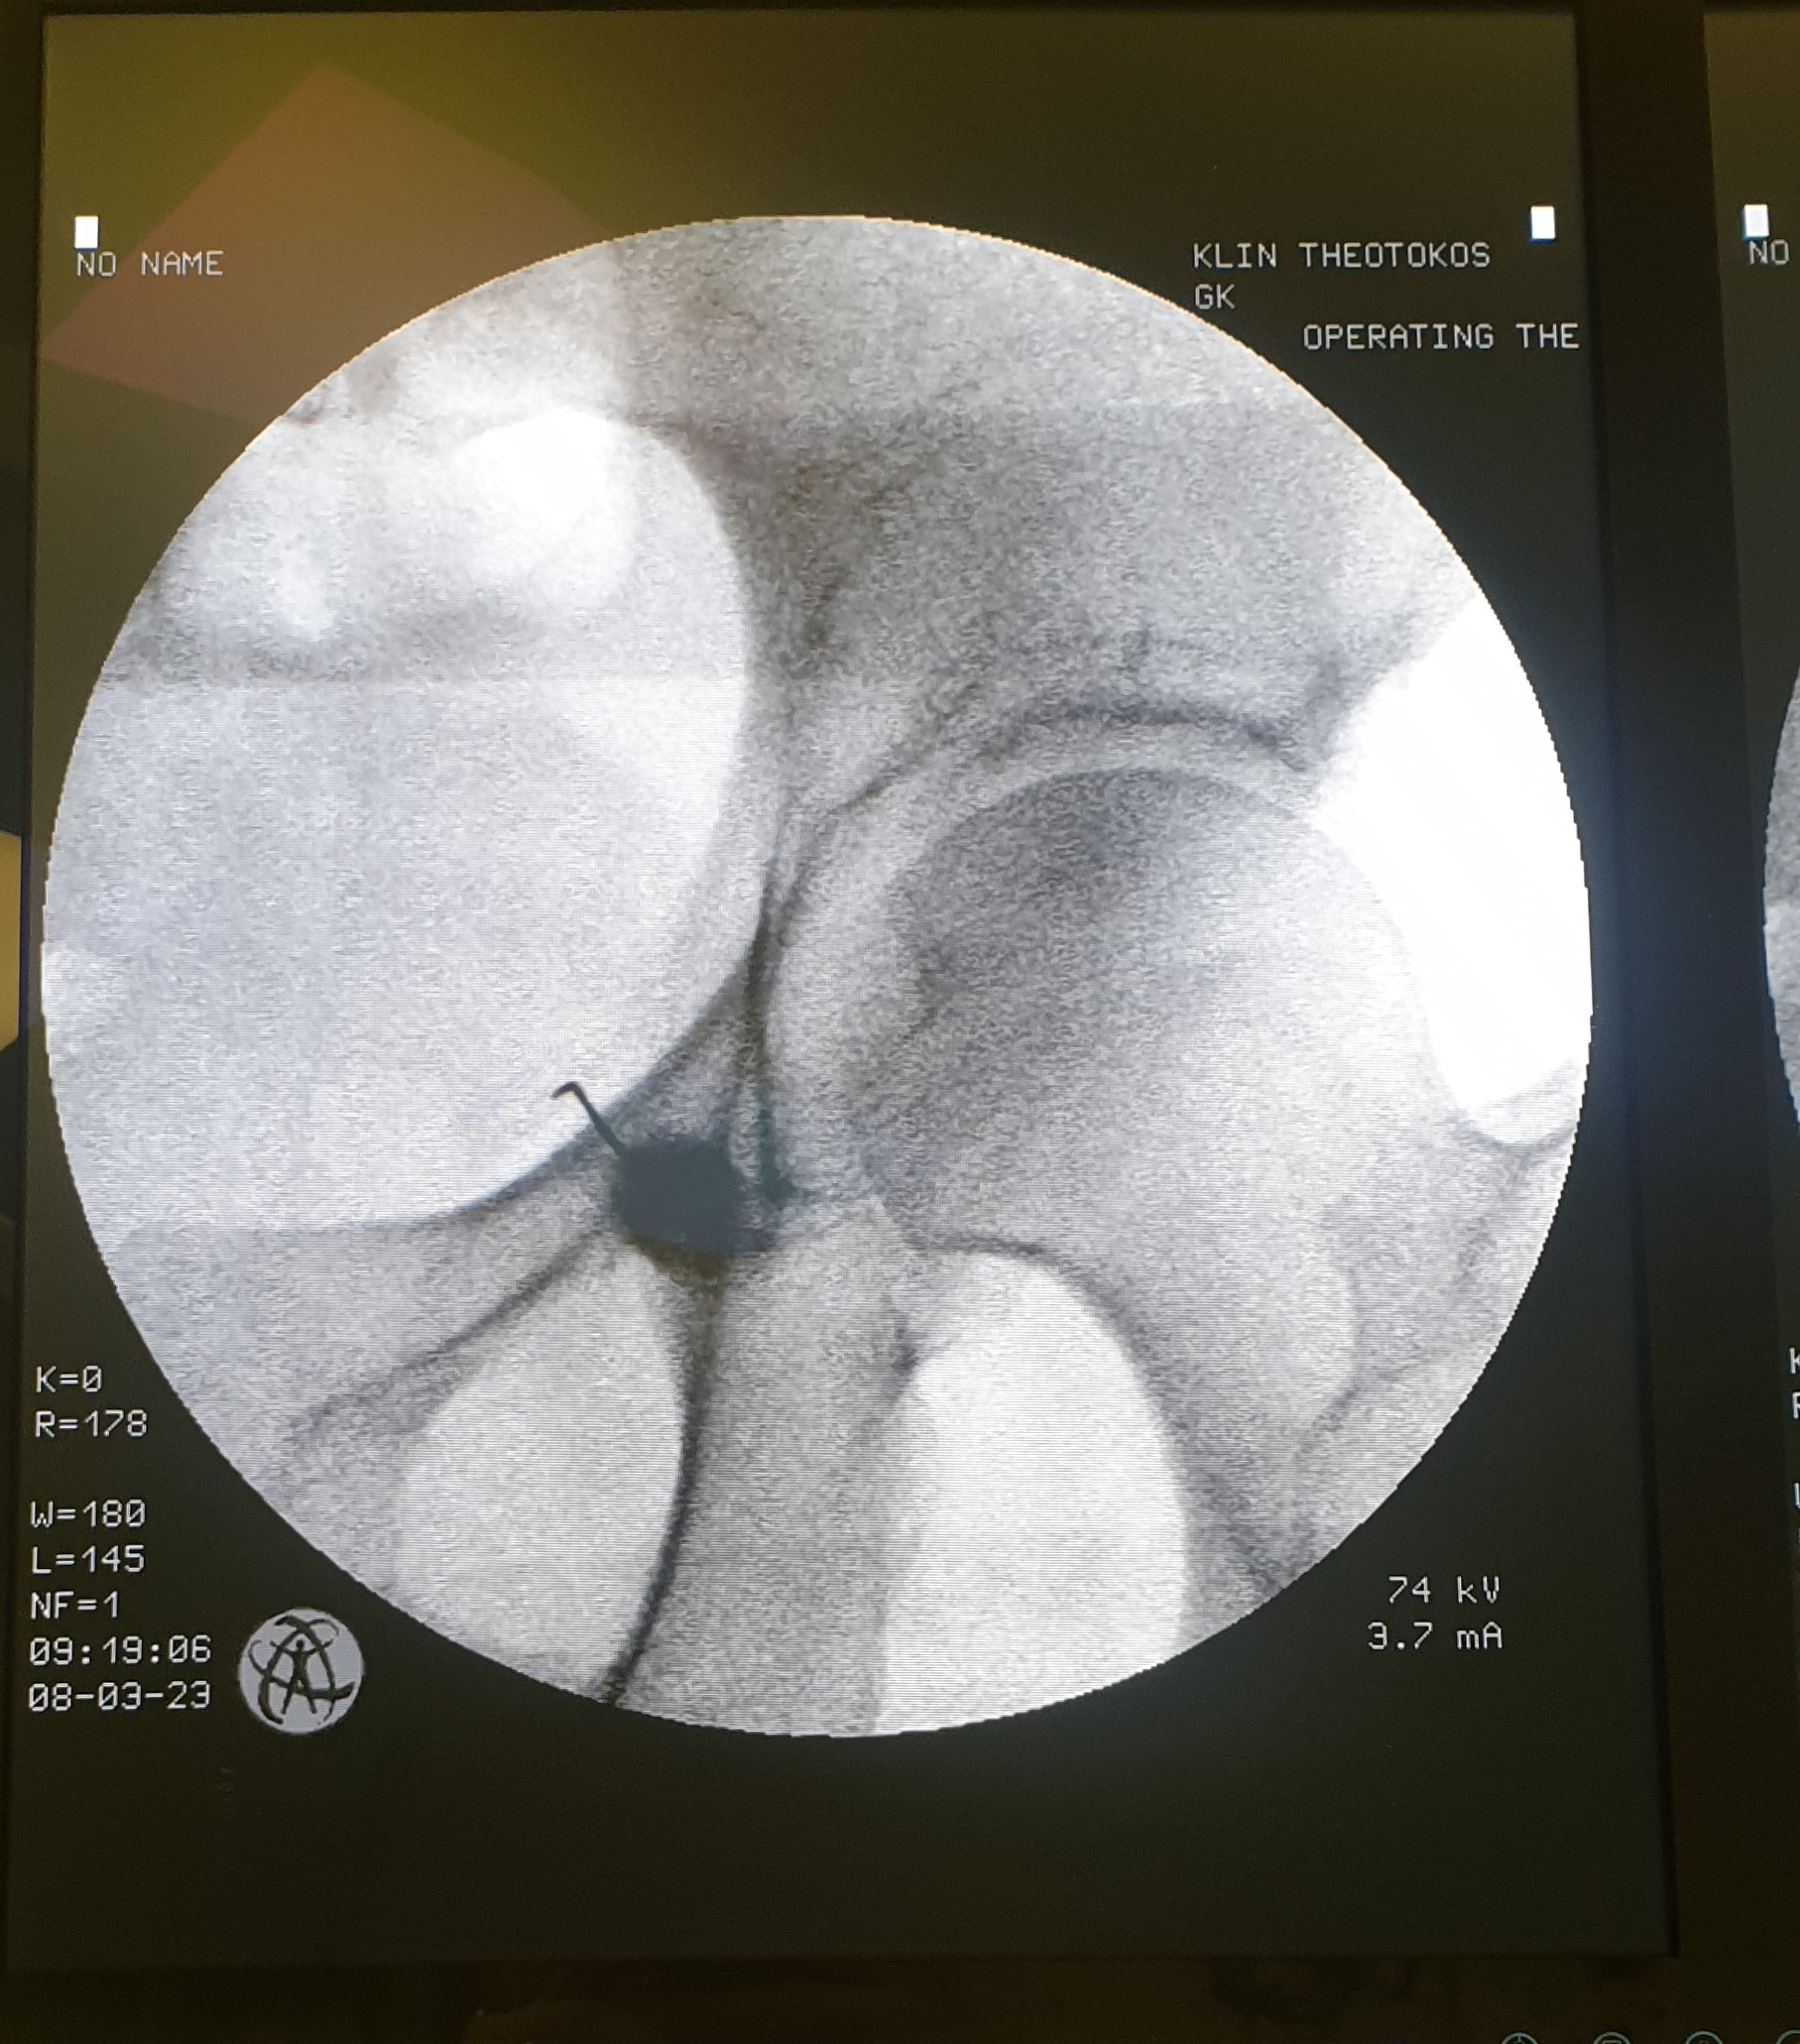

Πρόκειται για δυο τεχνικές που στοχεύουν στη διακοπή της μετάδοσης των σημάτων πόνου κατά μήκος των νευρικών οδών. Η πρώτη μέθοδος χρησιμοποιεί ραδιοσυχνότητες για να το πετύχει αυτό και η δεύτερη υγρό άζωτο που είναι ψυκτικός παράγοντας. Εφαρμόζονται σε ξύπνιο ασθενή με τοπική αναισθησία και κάτω από ακτινοσκοπική καθοδήγηση. Προσφέρουν σημαντική ανακούφιση για μήνες και επαναλαμβάνονται ως πράξεις εάν χρειασθεί μετά το πέρας της διάρκειας δράσης.

Ο κίνδυνος επιπλοκών είναι χαμηλός. Στις επιπλοκές ανήκουν η λοίμωξη, η ανάπτυξη αιματώματος, η βλάβη νευρικών και γύρω δομών. Η κινητική βλάβη του νεύρου αποφεύγεται με τη χρήση παλμικής ραδιοσυχνότητας ή κρυοπηξίας.